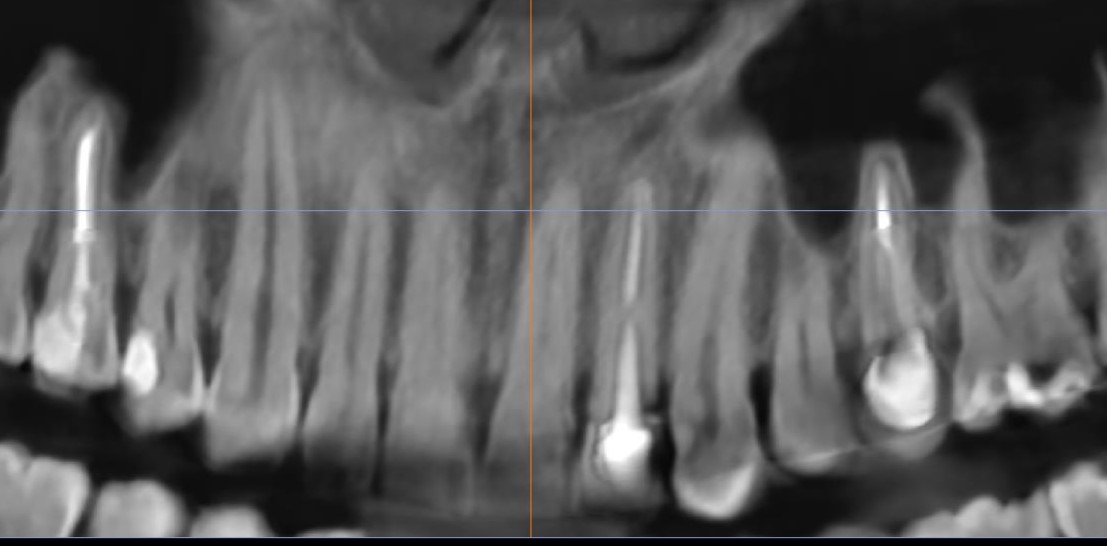

На рентгенологическом снимке видим что ранее в корень зуба был установлена вкладка